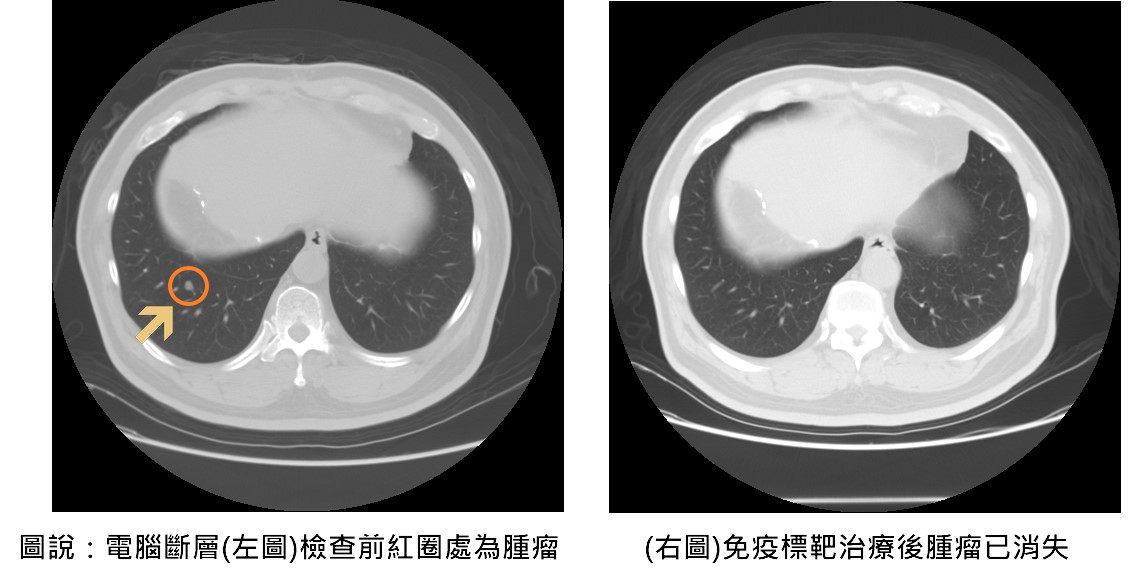

隨著2023年免疫標靶治療納入健保給付,大幅降低患者經濟負擔,也讓更多中晚期癌友得以接受有效治療。聯新國際醫院腸胃肝膽科余青殷醫師分享一位六十五歲患者,於兩年前接受肝癌切除手術,在術後例行追蹤時,發現甲型胎兒蛋白指數(AFP)持續飆高,以及肺部出現轉移的現象,經評估自體免疫狀況後,醫療團隊決定使用免疫標靶治療,採用第一線免疫標靶聯合療法-免疫藥物「癌自禦」與標靶藥物「癌思停」合併治療,三個月後AFP指數恢復正常,癌細胞亦完全消失,患者未出現任何不適或併發症,生活品質如常。

余青殷指出,過去中晚期肝癌的治療主要依賴單一標靶口服藥物,療效有限;而隨著免疫標靶聯合治療的發展,病患的整體存活期已顯著延長至近20個月,死亡風險亦降低約三成。值得注意的是,約10%以下的患者有機會成功治癒,讓腫瘤完全消失,這是以往中晚期肝癌不容易達到的效果。